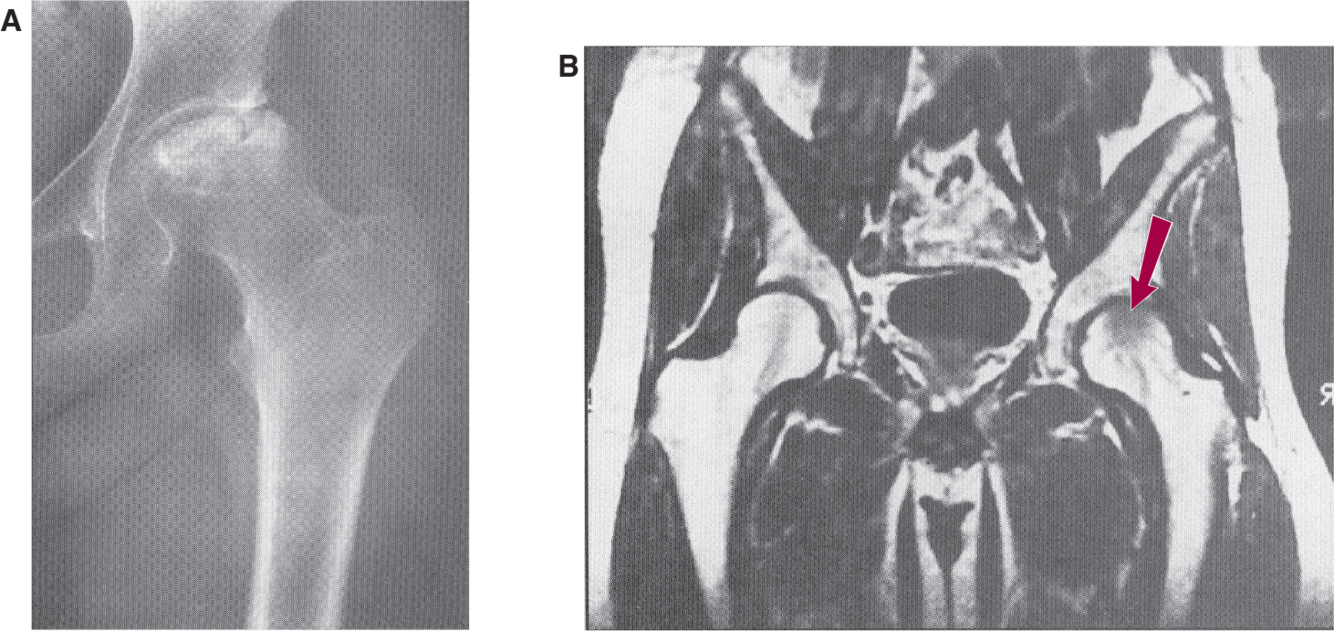

most common causes of AVN of the femoral head in adults?

alcohol and corticosteroid use